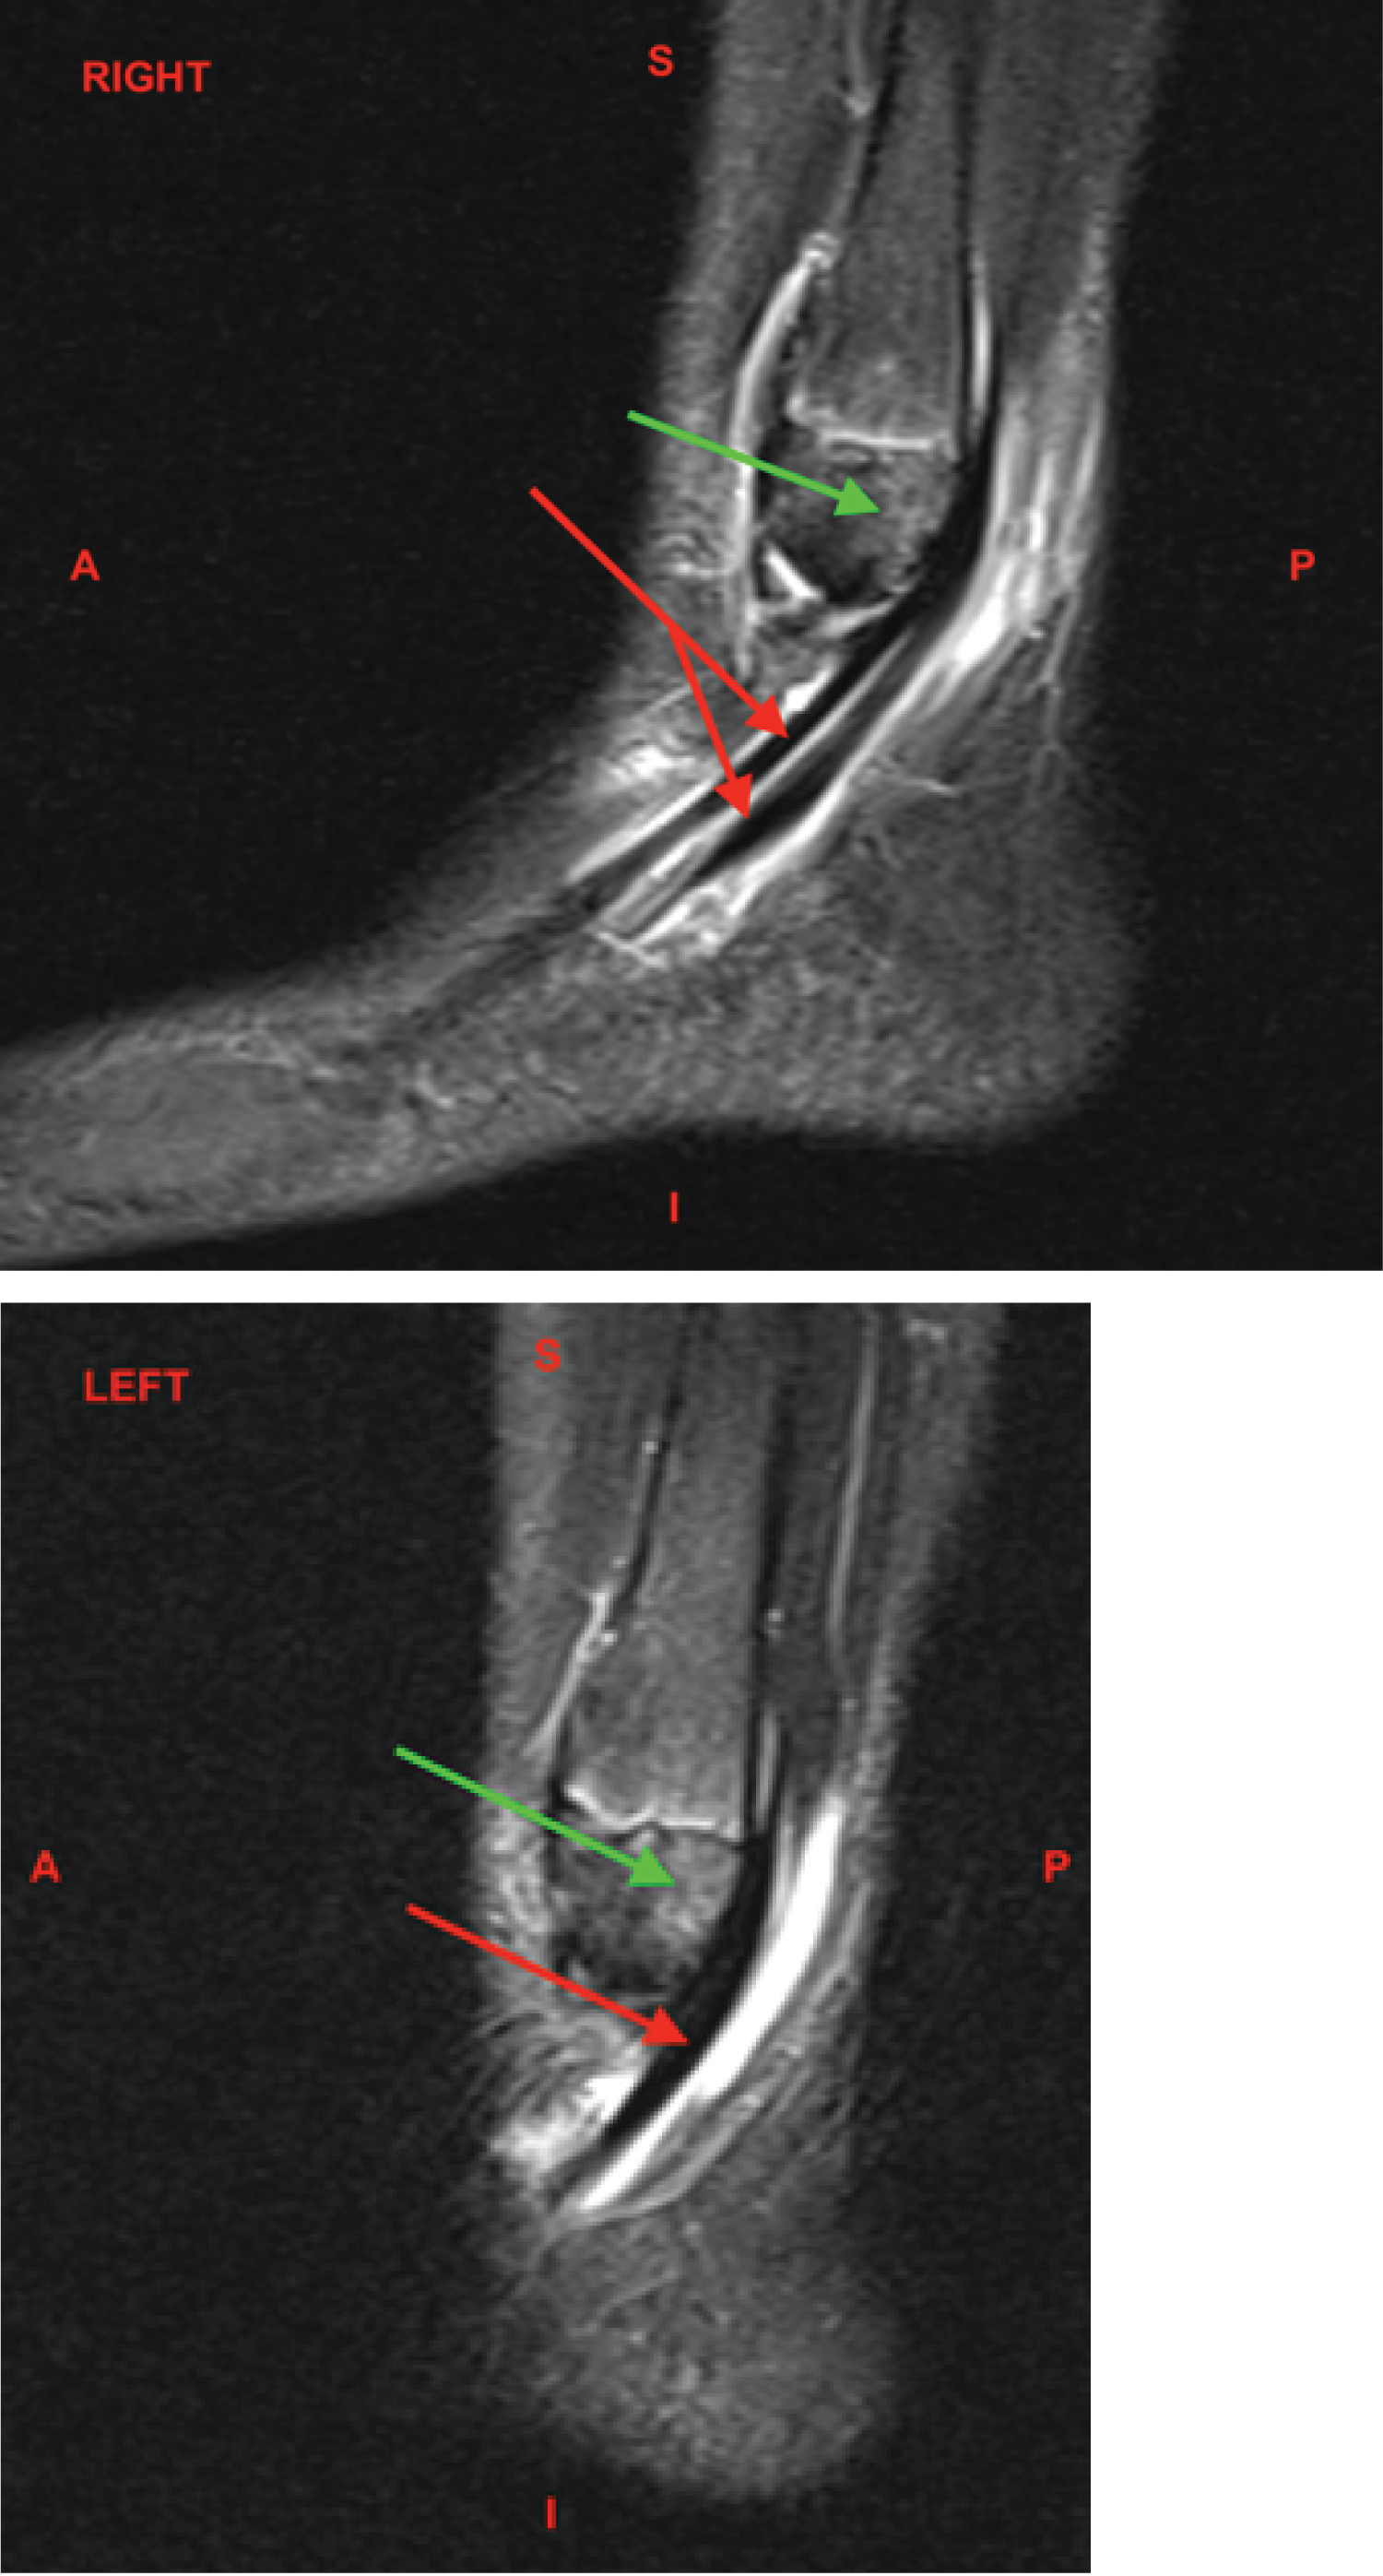

Figures 1 and Figure 2: MRI Ankle, Bilateral, Sagittal, T2 Fat Suppressed without contrast. The red arrows demonstrate the large amount of fluid signal intensity about the peroneus longus and brevis tendons indicative of tenosynovitis. The green arrows demonstrate the bone marrow edema within the lateral distal aspect of the lateral malleolus, likely reactive to the peroneus tendon subluxation.

S: Superior; I: Inferior; A: Anterior; P: Posterior View Figure 1 & 2

The patient was placed in bilateral controlled ankle movement (CAM) walker boots and ankle MRIs were completed 10 days after orthopedic consultation. The ankle MRIs were nearly identical bilaterally. Both demonstrated moderate to large amounts of fluid signal intensity around the peroneus longus and brevis tendons compatible with tenosynovitis. Minimal peroneus longus tendinosis was seen at the distal margin of the lateral malleolus bilaterally. Bone marrow edema was seen within the lateral distal aspect of the lateral malleolus, reactive from the peroneal tendon pathology. Soft tissue edema was seen surrounding the area. No injuries were seen to the articular cartilage. The extensor tendons, tibialis posterior, flexor digitorum longus (FDL), flexor hallicus longus (FHL), and Achilles tendon appeared intact. The anterior and posterior tibiofibular, talofibular, calcaneofibular, and deltoid ligaments appeared intact (Figure 3 and Figure 4).